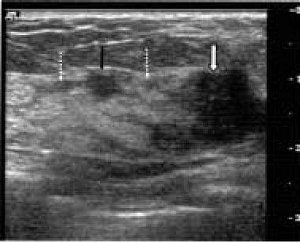

| Invasive ductal carcinoma in a 63-year-old woman. Above, ultrasound shows main tumor mass (white arrow) and satellite lesion (black arrow) with a ductal dilatation (dotted arrows) toward the nipple. The extent of intraductal component measured by ultrasound was 19 mm. Below, contrast-enhanced MRI study with maximum intensity projection (MIP) image shows main tumor (solid arrow) and satellite lesions (dotted arrows) in 3D coronal image. The extent of intraductal component measure by MRI was 18 mm. Histopathological studies diagnosed the invasive ductal carcinoma with satellite lesion and an intraductal component of 18 mm toward the nipple. |

| Sundararajan S, Tohno E, Kamm H, Ueno Ei, Minami M, "Detection of Intraductal Component around Invasive Breast Cancer Using Ultrasound: Correlation with MRI and Histopathological Findings," Radiation Medicine, Vol. 24:2, pp. 108-114, 2006, Figure 2. |